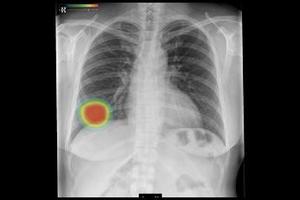

「医療クラウドサービス」は,「SYNAPSE LEAD Cloud」からクラウドサーバーにアップロードされた画像に対し,選択した読影支援機能の解析結果をビューワ上で参照できるサービス。ユーザー登録後,専用ポータルサイトから「胸部X線CADサービス」や「肺結節検出サービス」など,5つの解析機能の中から必要なものを選択するだけで,簡単に利用できる。料金プランは,利用回数に応じた従量課金と,一定期間利用できる定額利用の2種類を用意しており,導入コストを抑えながら,目的や運用に応じた柔軟な活用が可能である。さらに,本格導入前に無料トライアルから利用を開始することもできる。

胸部X線CADサービス*6 |

*6 胸部X線CADサービス(CXR-AID)は,「胸部X線画像病変検出ソフトウェア CXR-AID」の【類型1】によって提供されるサービス。販売名:胸部X線画像病変検出(CAD)プログラム LU-AI689型 承認番号:30300BZX00188000